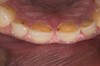

Figure 14  Postoperative smile.

Figure 14